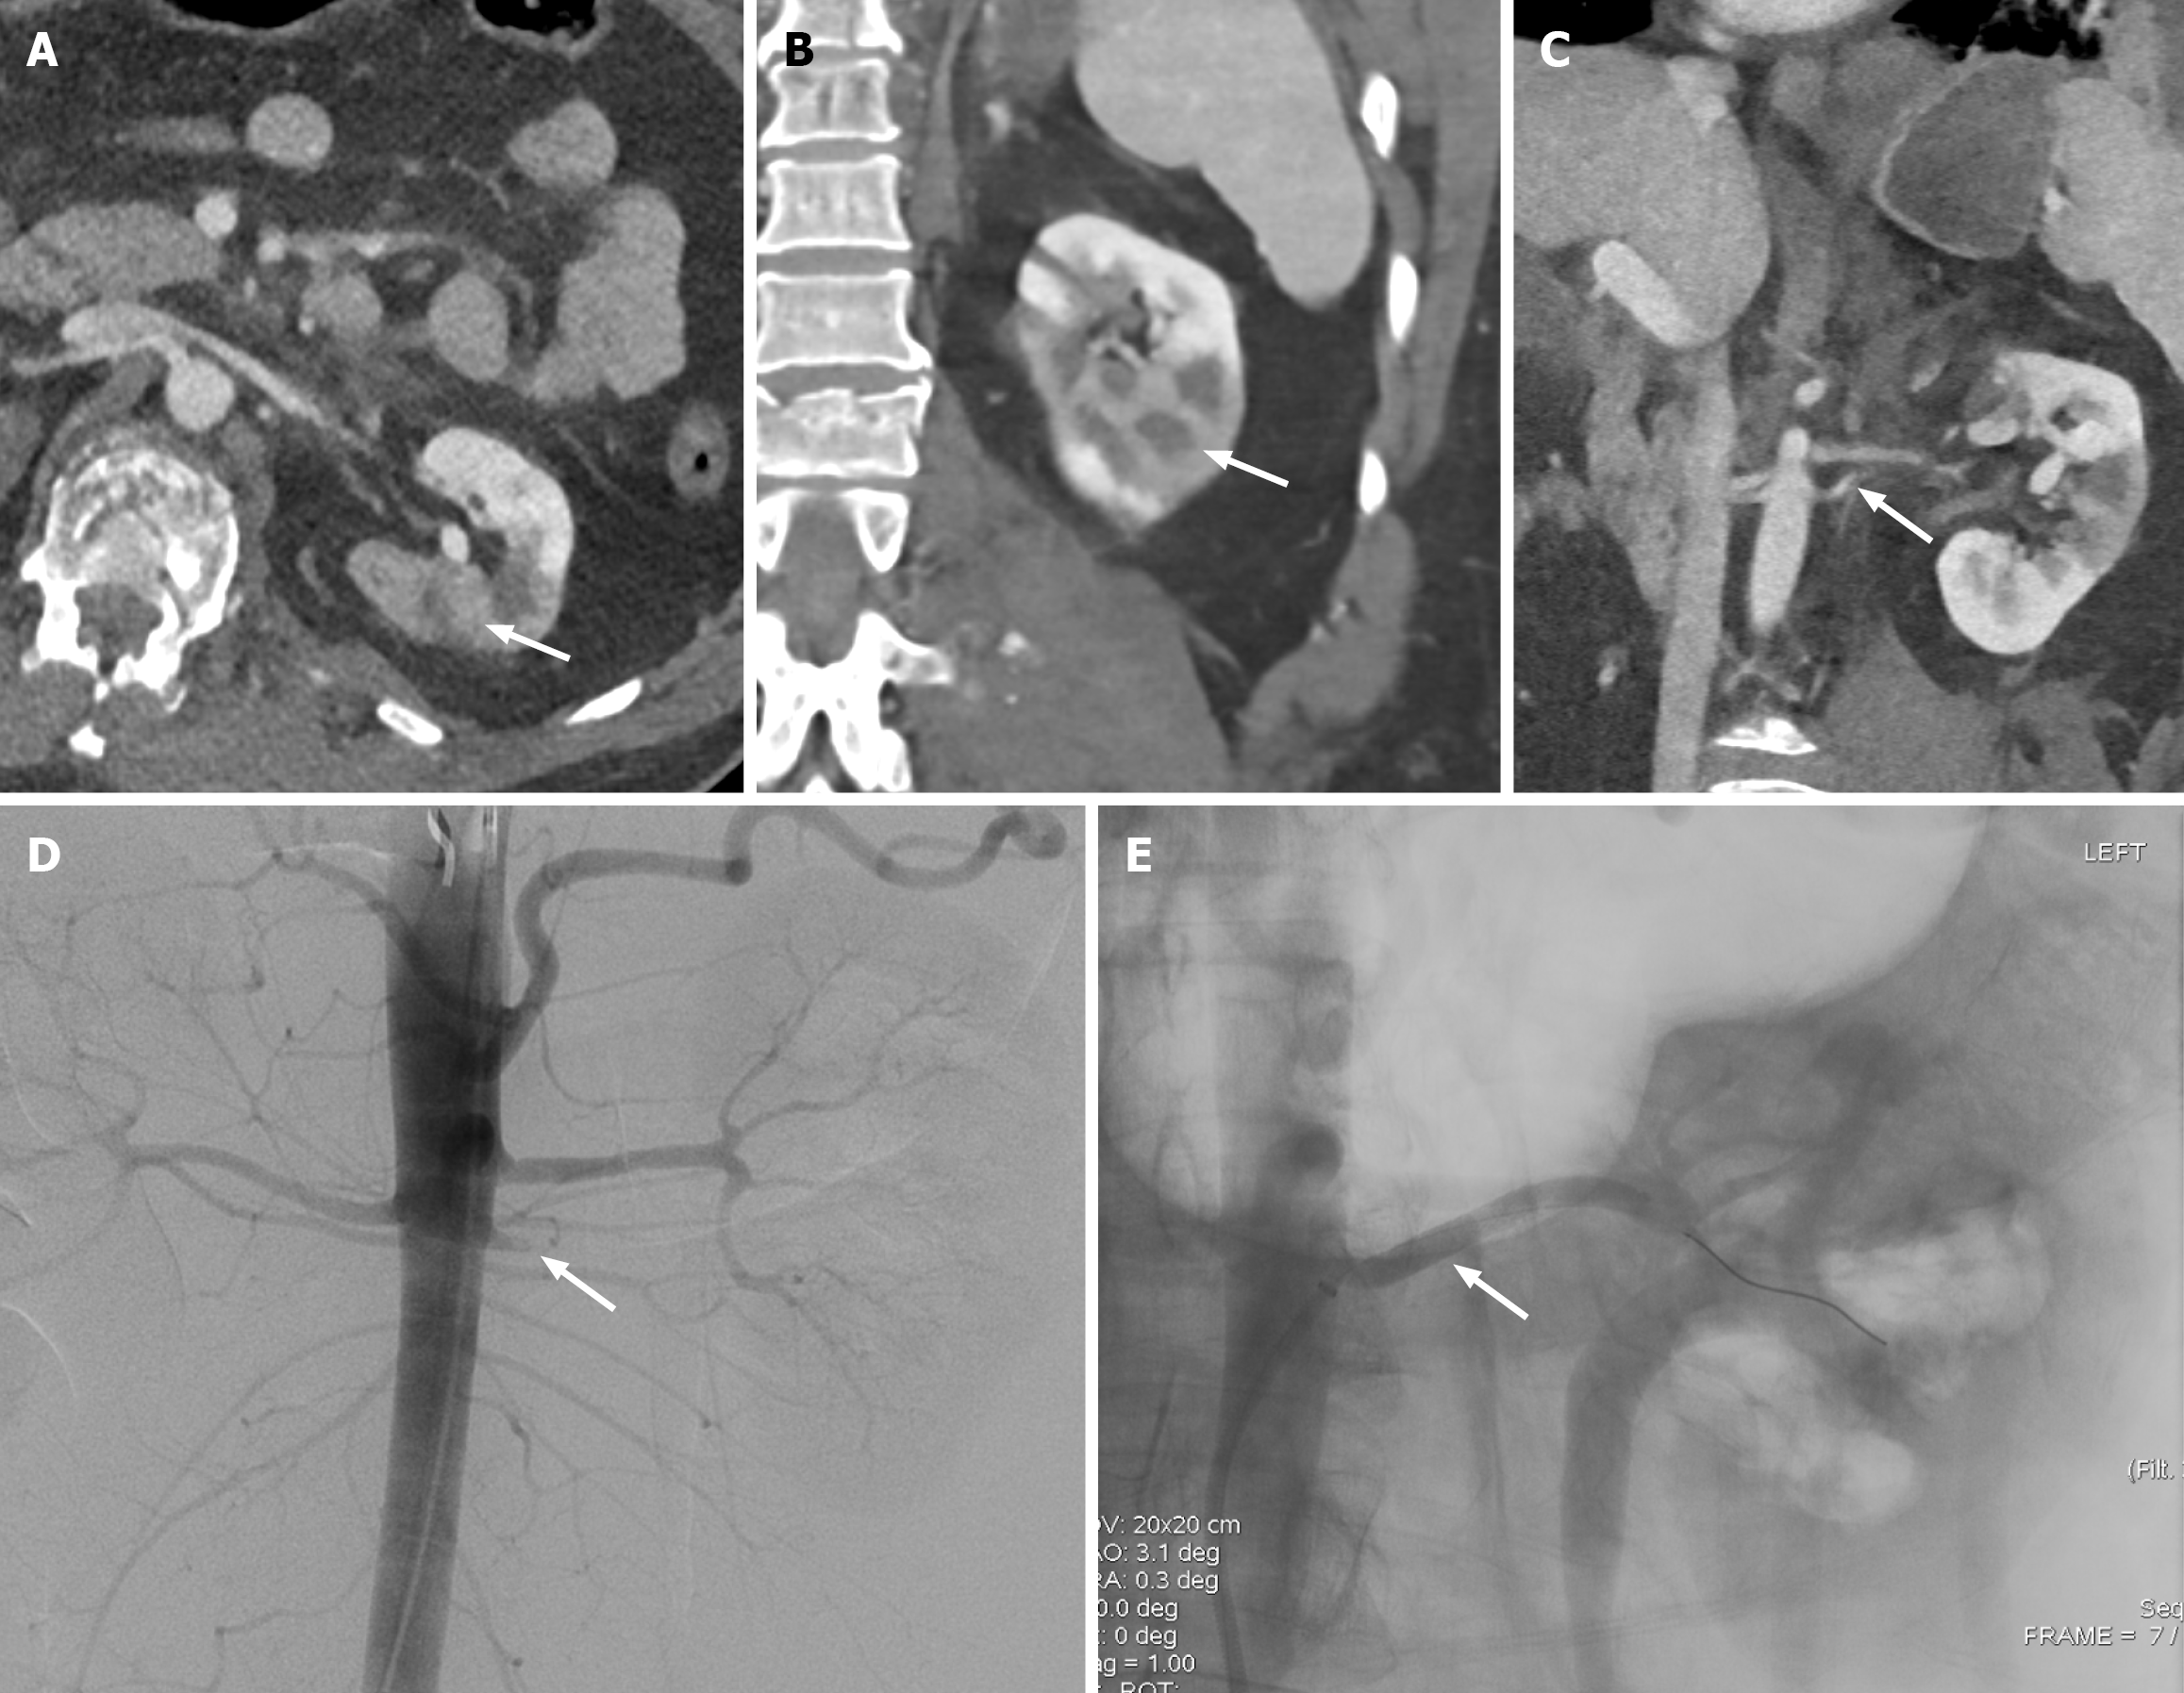

Figure 5 Renal infarct.

A: Axial computed tomography of the abdomen shows segmental absent enhancement of the left kidney (white arrow); B: Coronal computed tomography of the abdomen shows segmental absent enhancement of the left kidney (white arrow); C: The infarction is attributed to the thrombosis of the accessory left renal artery (white arrow). These findings correspond to grade IV renal injury; D: Patient underwent left renal angiogram confirming the thrombotic occlusion of the accessory left renal artery (white arrow); E: Successful deployment of the bare-metal stent with improved flow (white arrow).